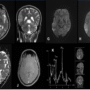

Initial MRI

ØFig A-D (initially performed MRI) shows predominantly cortical T2W/FLAIR hyperintensity in left parasagittal parieto-occipital lobes. No true restricted diffusion or bleed noted.

Ø(Repeat MRI after 3 months) Fig E-I show T2W/FLAIR hyperintensity with high signal intensity on DWI & ADC representing T2-Shine through in the right parieto-temporal cortex & subcortical white matter

ØFig J (post contrast administration) did not reveal significant enhancement.

ØFig K (MRS) showed elevated lactate is noted.